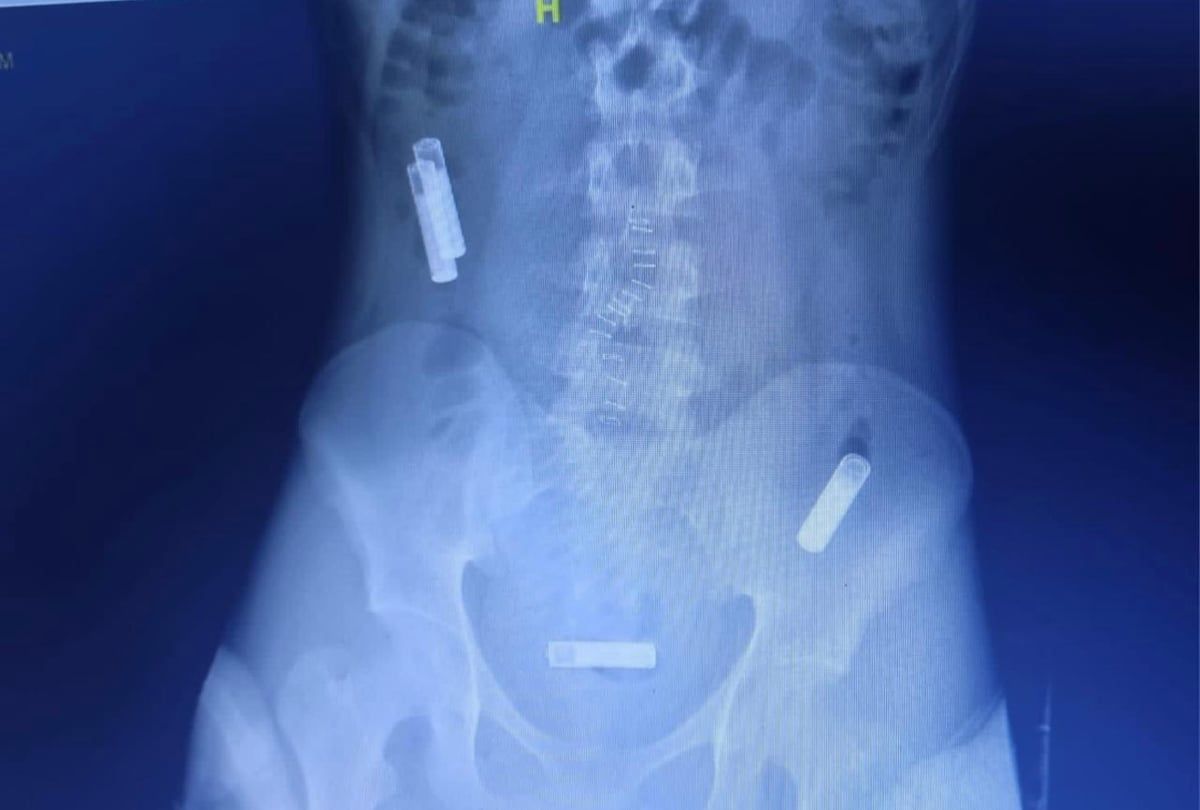

نجح فريق طبي بقسم المناظير والجهاز الهضمي بمستشفى النور التخصصي بمكة المكرمة، في استخراج ٣ بطاريات ريموت تلفزيون، من بطن مريض نفسيّ، بعد ابتلاعها؛ متوهمًا من هذا التصرف أنه طبيعي.

وبحسب المعلومات الطبية؛ فإن المريض حضر إلى قسم الطوارئ والحوادث وهو يشتكي من ألم بالمعدة مع غثيان وقيء، وبعد عمل الفحوصات الطبية والأشعة المقطعية؛ اتضح وجود 3 بطاريات داخل بطن المريض.. وعلى الفور تم عمل عملية المنظار الذي استغرق 35 دقيقة، وتم استخراج البطاريات من الأمعاء الدقيقة والقولون للمريض.